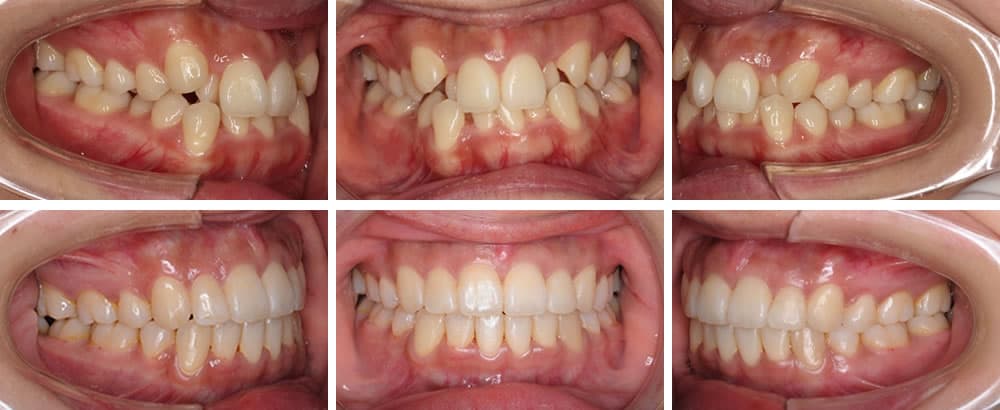

叢生(八重歯など)

叢生は歯が様々な向きに生え、ばらばらな状態の歯並びです。歯が重なった部分のケアが難しいため、虫歯や歯周病リスクが高くなります。また、見た目も悪くコンプレックスに感じる方も少なくありません。